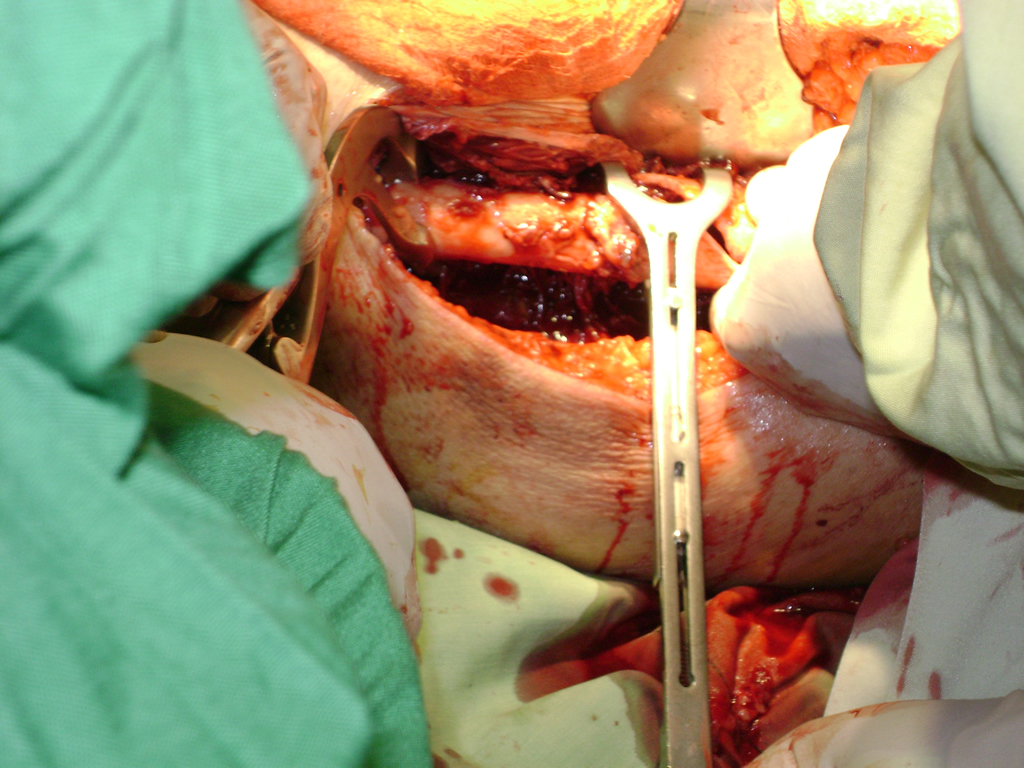

A menudo se recomienda la cirugía para reparar la fractura debido a dichos riesgos.